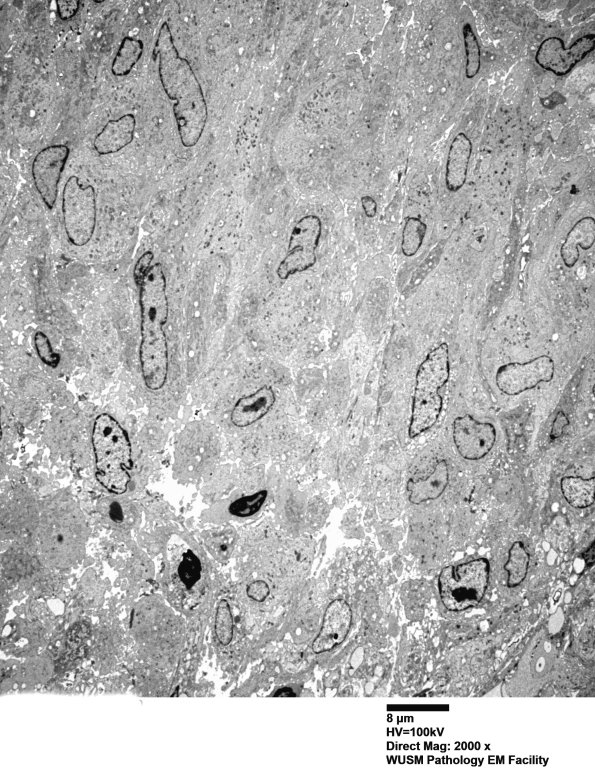

A low magnification image of the granuloma. (electron micrograph)